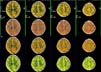

¥ Multislice perfusion study of the brain

¥ Normal Brain

0.75-s/rot., 0.5-mmx4, Pitch 3.0, 200-mAs